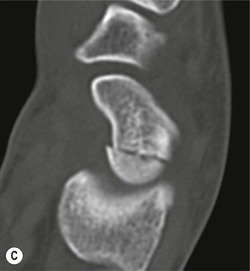

Radiological signs of avascular necrosis (AVN) include sclerosis of the proximal pole, which may progress to articular collapse and bone fragmentation. CT is used to assess the state of fracture union (Fig. 46-24). Signs of AVN on MRI include low SI sclerosis on T1-weighted (T1W) images and short T1 inversion recovery (STIR) images. Marrow oedema on STIR images is an indicator of persistent vascular perfusion in the proximal segment. The absence of enhancement with gadolinium contrast medium on fat-saturated T1W images in areas of sclerosis is a reliable indicator of lack of vascularity15 (Fig. 46-25).

Spontaneous AVN of the lunate is known as Keinböck's disease. The radiographic and MRI features are the same as AVN of the scaphoid (Fig. 46-26). It may be associated with negative ulnar variance (short ulna). Advanced bony collapse in both proximal scaphoid fractures and AVN of the lunate results in late-stage secondary osteroarthritis.